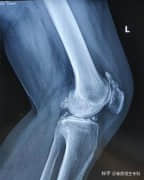

髌骨脱位、膝关节疼痛原因